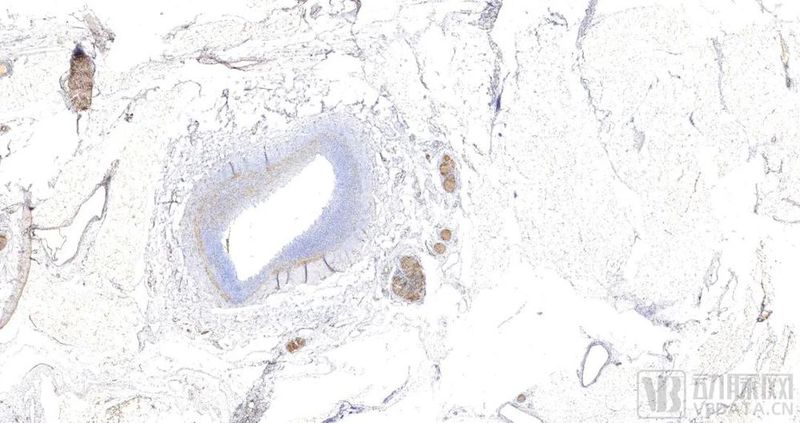

公司专利技术(组织固定液)制备的HE染色肠粘膜组织(上)、心脏瓣膜赘生物(中)和免疫组化染色(下)

通过产品的技术创新,比如通用型组织细胞固定液(专利号201911335152.6)、脑组织固定液(专利号201911335152.6)和骨组织脱钙液(专利号201911335152.6),除了摒弃了传统福尔马林固定液的刺激性和毒性外,在样本后续进一步检测(如免疫组化)应用时减少了对组织的处理环节,降低了抗原修复的难度,保证了检测结果的可靠性。